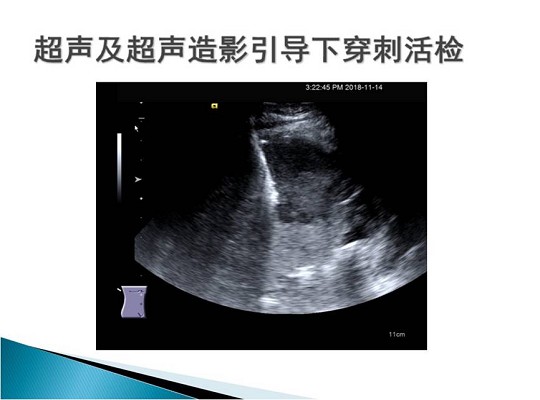

第三届中国超声造影大会病例大赛北医三院超声科获奖病例展示(二)